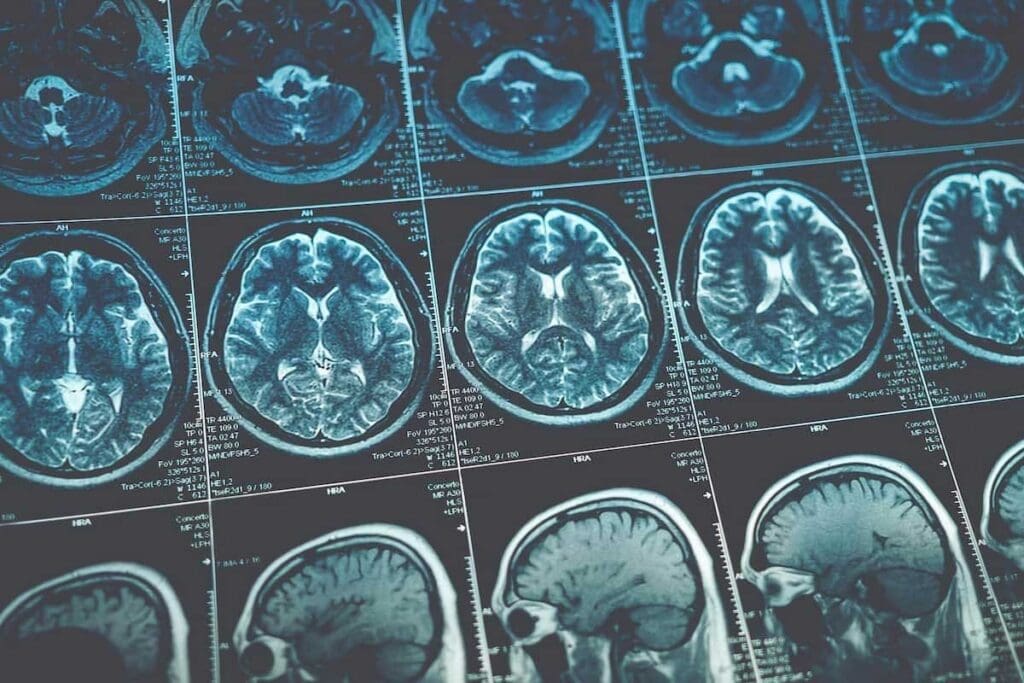

Advanced Imaging Techniques

Advanced imaging is key in diagnosing and staging brain tumors. MRI (Magnetic Resonance Imaging) and CT (Computed Tomography) scans help us see the tumor’s size, location, and type. These tools show how the tumor affects the brain and guide treatment.